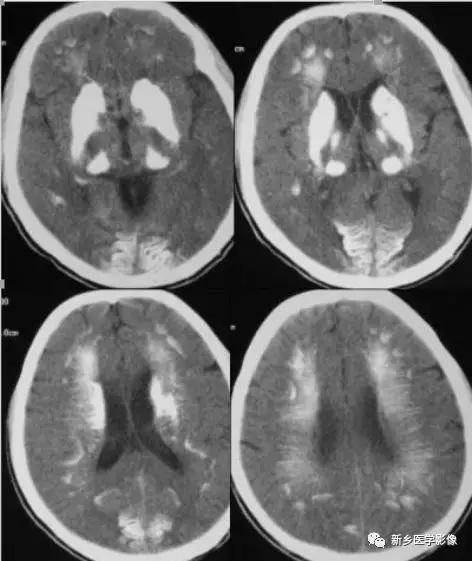

临床表现:与低血钾有关,主要表现有癫痫发作、注意力不集中、记忆和定向障碍、白内障、皮肤粗糙。生化检查特点:血清钙降低,血清磷增高。CT表现:钙化多位于基底节区,呈双侧对称性。在丘脑、小脑齿状核、大脑半球皮层下级皮髓质交界区,也可出现两侧较对称,呈斑片状、条形、月牙状或点状钙化。

十一、特发性家族性脑血管铁钙质沉着症(Fahr’s病)

病理学上以双侧基底节区铁钙质沉积为特征。也可发生于丘脑、小脑齿状核和皮质下区。CT表现为双侧基底节区对称性钙化,呈均质较高密度,轻者钙化仅局限于苍白球、尾状核、壳核和丘脑,严重者大脑半球皮层下、小脑齿状核和脑回呈弥漫性广泛性钙化。